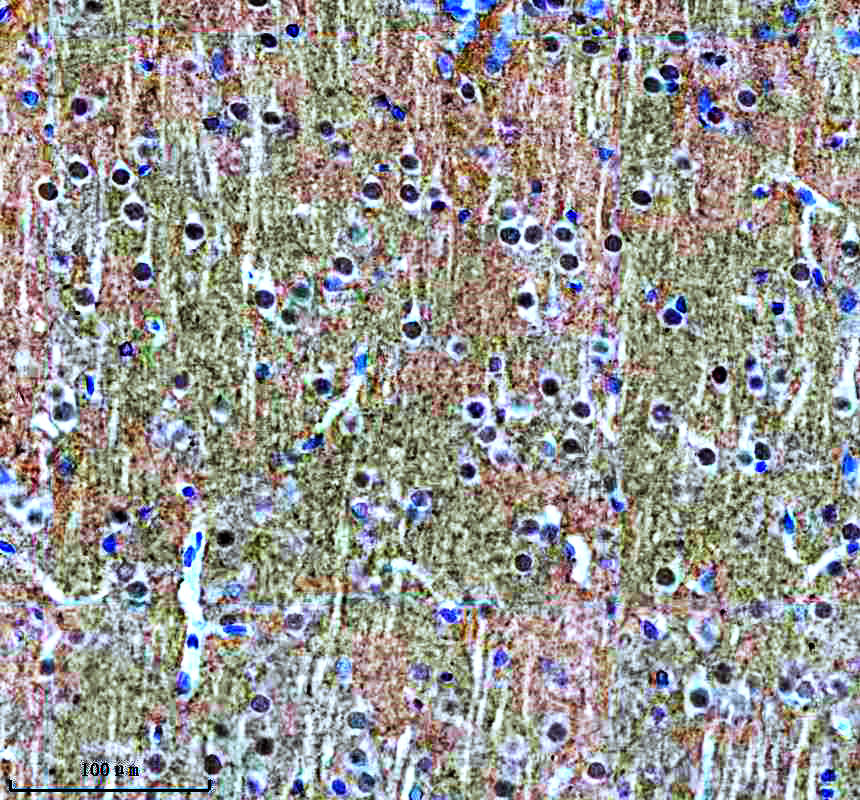

IHC analysis of SNCA using anti-SNCA antibody (BM4024) .

SNCA was detected in a paraffin-embedded section of mouse brain tissue. The tissue section was incubated with rabbit anti-SNCA Antibody (BM4024) at a dilution of 1:200 and developed using HRP Conjugated Rabbit IgG Super Vision Assay Kit (Catalog # SV0002) with DAB (Catalog # AR1027) as the chromogen.